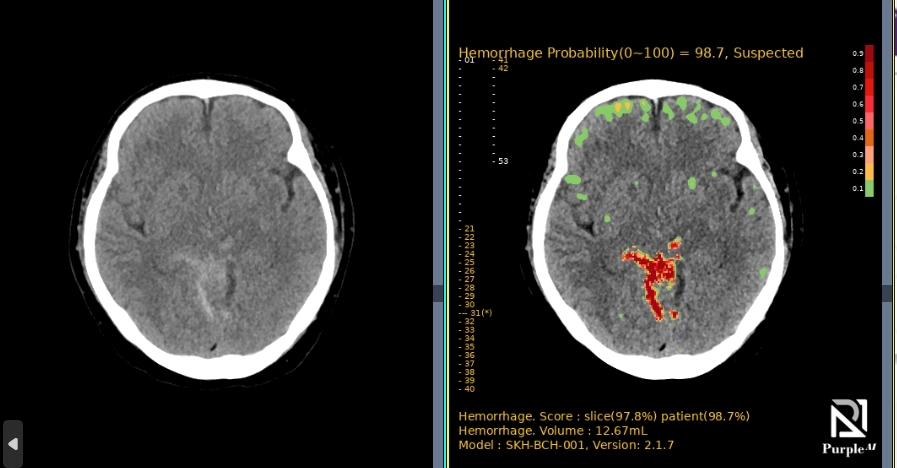

Download BrochureAI-powered diagnostic support for rapid, accurate detection and localization of brain hemorrhages on non-contrast CT, with ROI visualization and volume quantification to help radiologists assess hemorrhagic regions.

A multi-center, randomized, retrospective crossover superiority pivotal study, demonstrating high performance across all major ICH subtypes.

Performance Metrics

| Metric | Performance Result (Patient-wise) |

|---|---|

| Centers | 13 US clinical sites |

| Trial Size | 394 brain CT images (198 positive / 196 negative cases) |

| AUC | 98.64% |

| Sensitivity | 95.45% |

| Specificity | 98.47% |

| Speed (Notification Seconds) | Average time was 16.39 ± 5.46 seconds |

| Subtype Performance | 94.7%~100% |

| Data Diversity | The trial included diverse racial demographics (Alaskan Native, Asian, Black, White, etc.) |